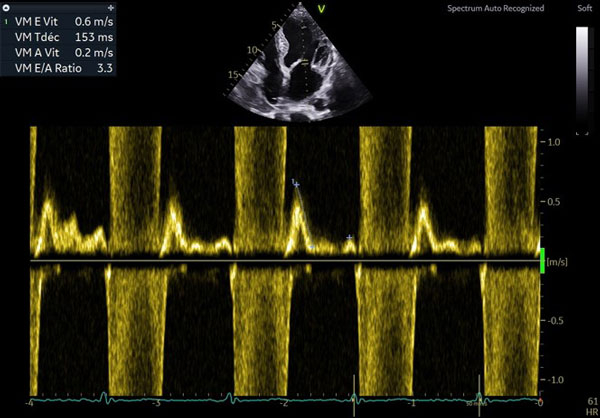

ETT de contrôle à 6 mois

- VG dilaté (DTDVG 58mm, VTDVG 78mL/m²) hypertrophié ( SIV 14mm ), FEVG modérément altérée, SBP 42%

- Petite IM centrale, pas de valvulopathie aortique

- PRVG normales, profil mitral en trouble de relaxation onde E 0.4m/s

- OG sévèrement dilatée

- VD non dilaté normokinétique

- PAPS estimées à 25mmHg, POD basse VCI fine compliante

- Péricarde sec

Figure 3 : profil mitral normal